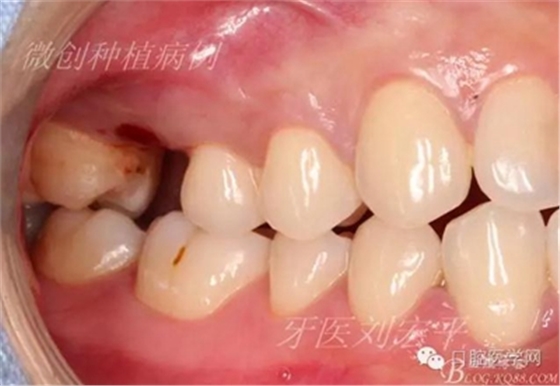

咬合照片